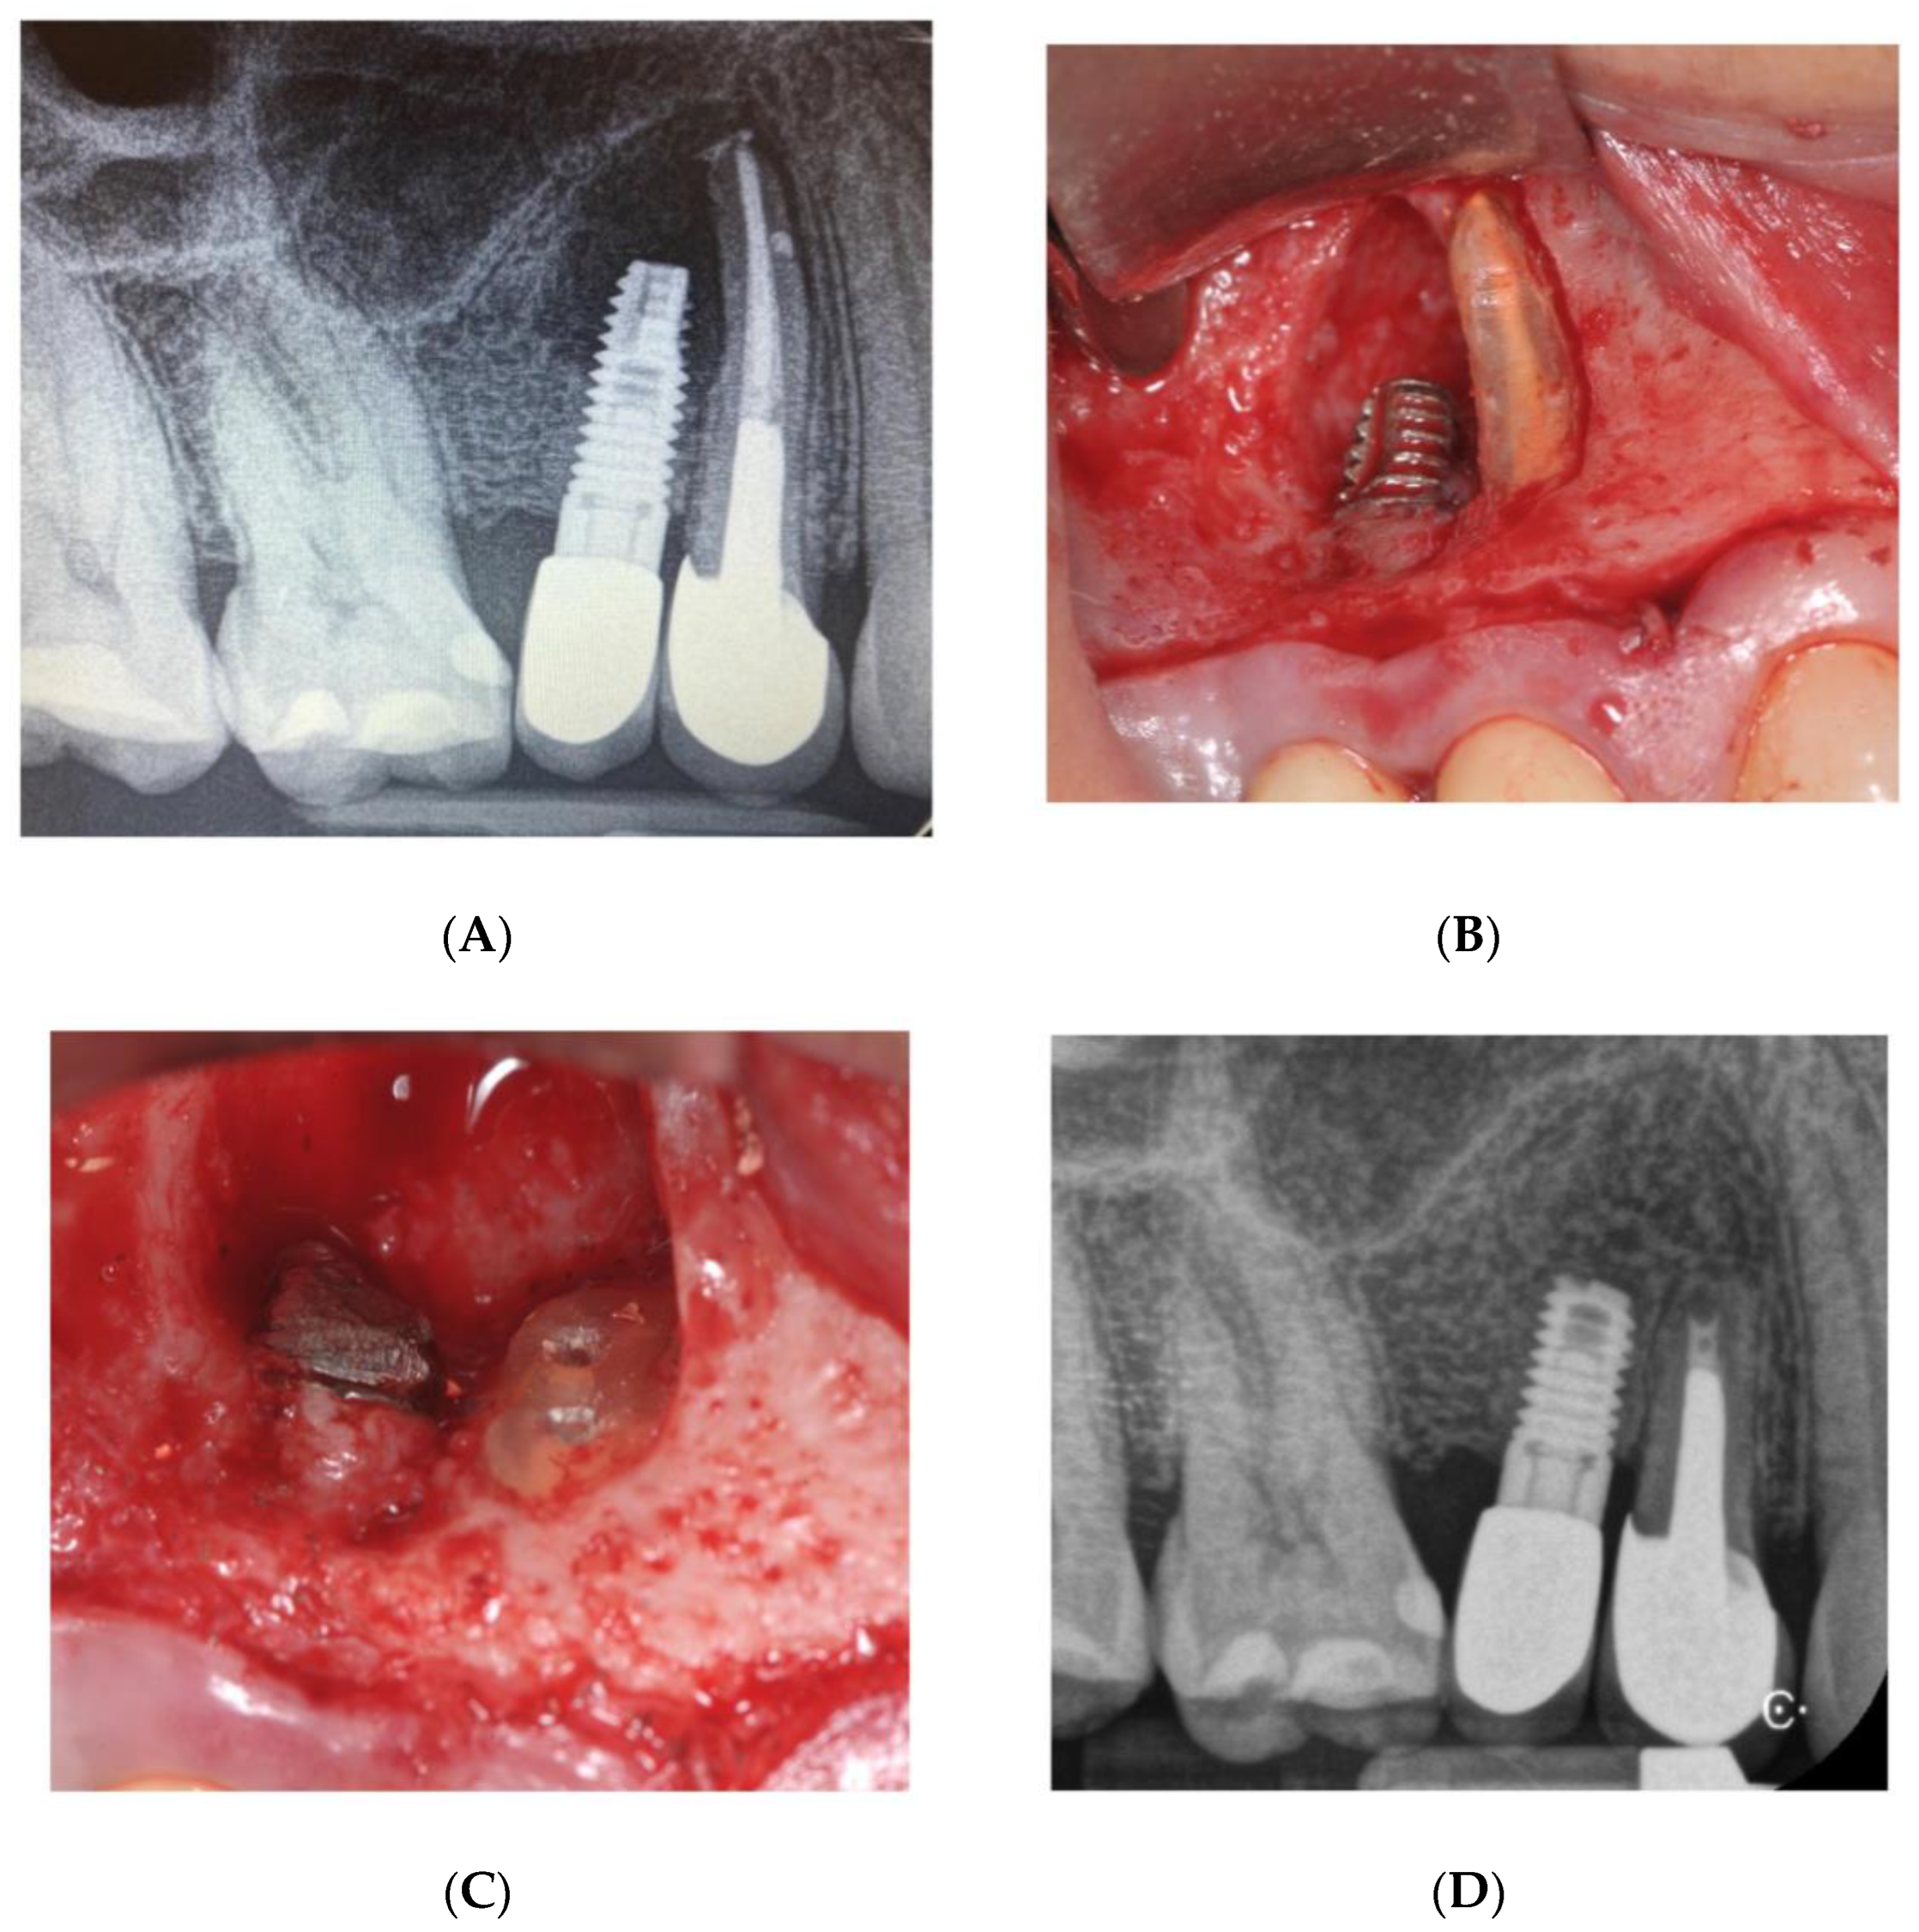

3. Case Report n. 2